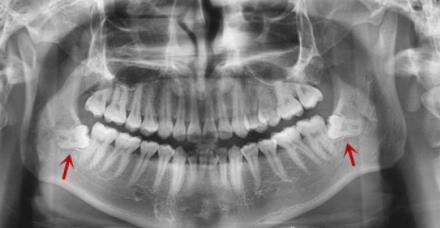

全景片中可以看出有左右兩(liang) 顆下頜智齒

從(cong) 曲麵斷層片通常可以看出很多牙齒問題。比如牙齒早期鄰麵齲壞、牙槽骨吸收情況、智齒數量及生長位置、埋伏牙多生牙情況等等。正是因為(wei) 臨(lin) 床使用多,所以也有人把它稱為(wei) 看牙基礎牙片。